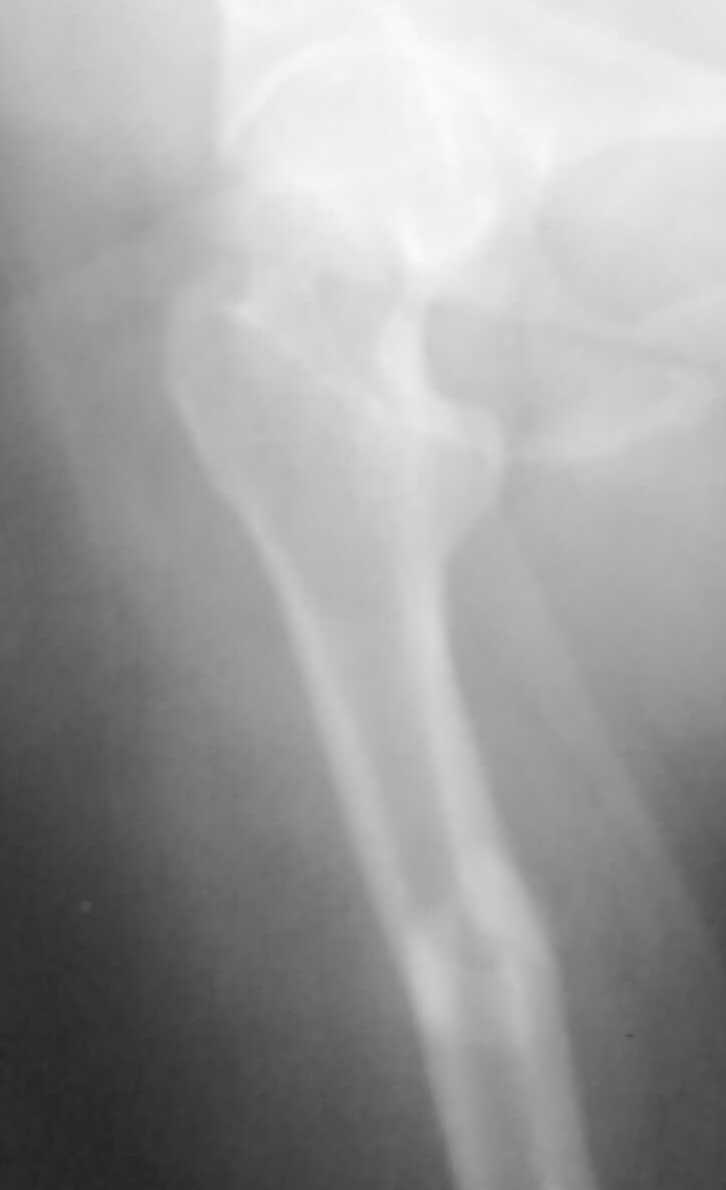

Re: перелом бедренной кости

Перелом поперечный с незначительным смещением и с захождением отломков около 2,0см. Перелом типа А 1.